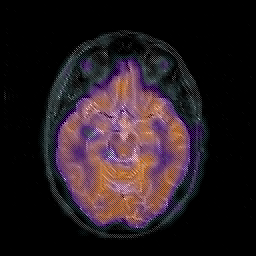

Glioblastoma multiforme overlay -- Slice #22

[Home][Help][Clinical][Tour 1][Tour 2][Tour 3] Slice 22